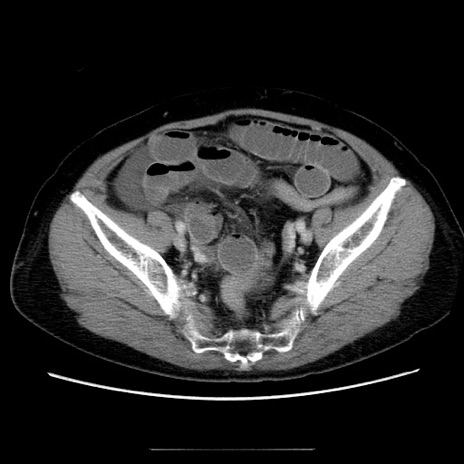

症例5(横断像)

【症例】70歳代女性

【主訴】お腹が張る

【現病歴】1週間くらい前から腹部膨満の自覚あり。昨日夜から増悪したため、本日救急外来受診。

【身体所見】意識清明、BT 36.5℃、BP 165/106mmHg、HR 80bpm、SpO2 98%、腹部:膨満、軟、自発痛・圧痛なし、触診にて不快感あり、腸蠕動音:減弱

【データ】WBC 12600、CRP 1.04